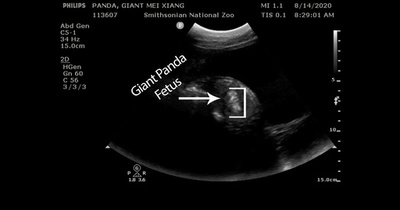

ジャイアントパンダが妊娠、数日内に出産か 米国立動物園